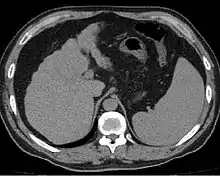

Other scans include CT of the abdomen and MRI.[35] A CT scan is non-invasive and may be helpful in the diagnosis.[35] Compared to the ultrasound, CT scans tend to be more expensive. MRI provides excellent evaluation; however, is a high expense.[35]

Liver cirrhosis on CT imaging of the abdomen in transverse view